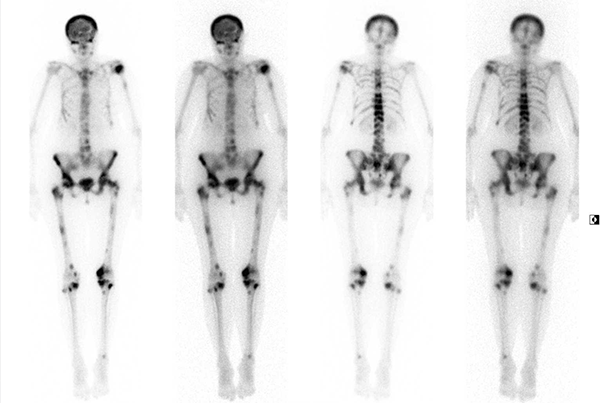

Röntgen, Szintigraphie, Strahlentherapie, Mammographie, Schilddrüsensprechstunde